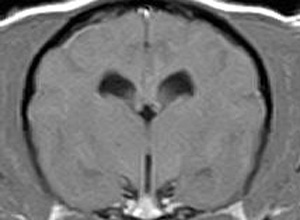

けいれん発作が出るワンちゃんが来院されました。MRI検査では脳に構造上の異常を認めず、脳脊髄液検査でも異常を認めず、特発性てんかんとの診断でお薬での治療となりました。発作は現在のところ、お薬で良好にコントロールされています。